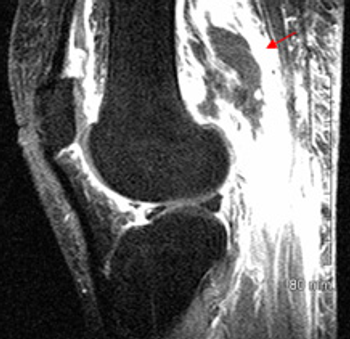

Separate newly published assessments describe hyaluronic acid injections and debridement after meniscectomy of scant clinical value for longstanding relief of knee pain, whatever small statistical significance may turn up in some studies.